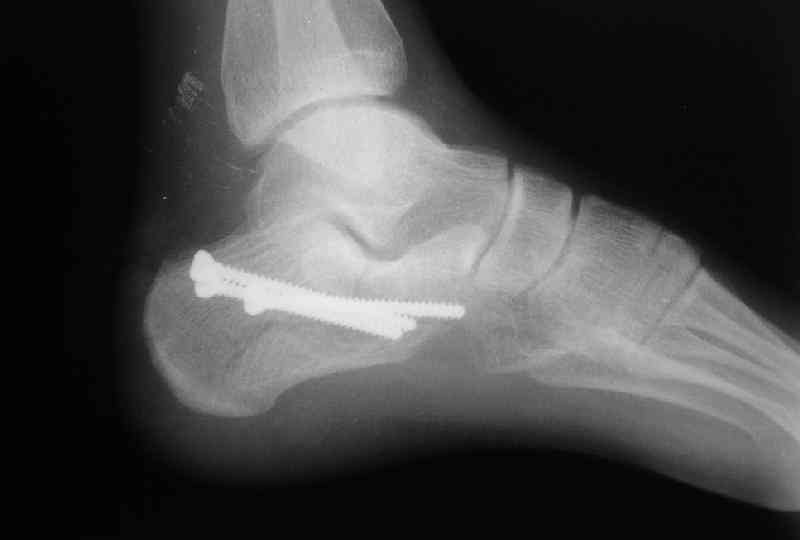

Re: Перелом пяточной кости

Какой предпочитаете доступ? Нет ли показательных рентгенснимков?

Открытый и закрытый способы лечения.